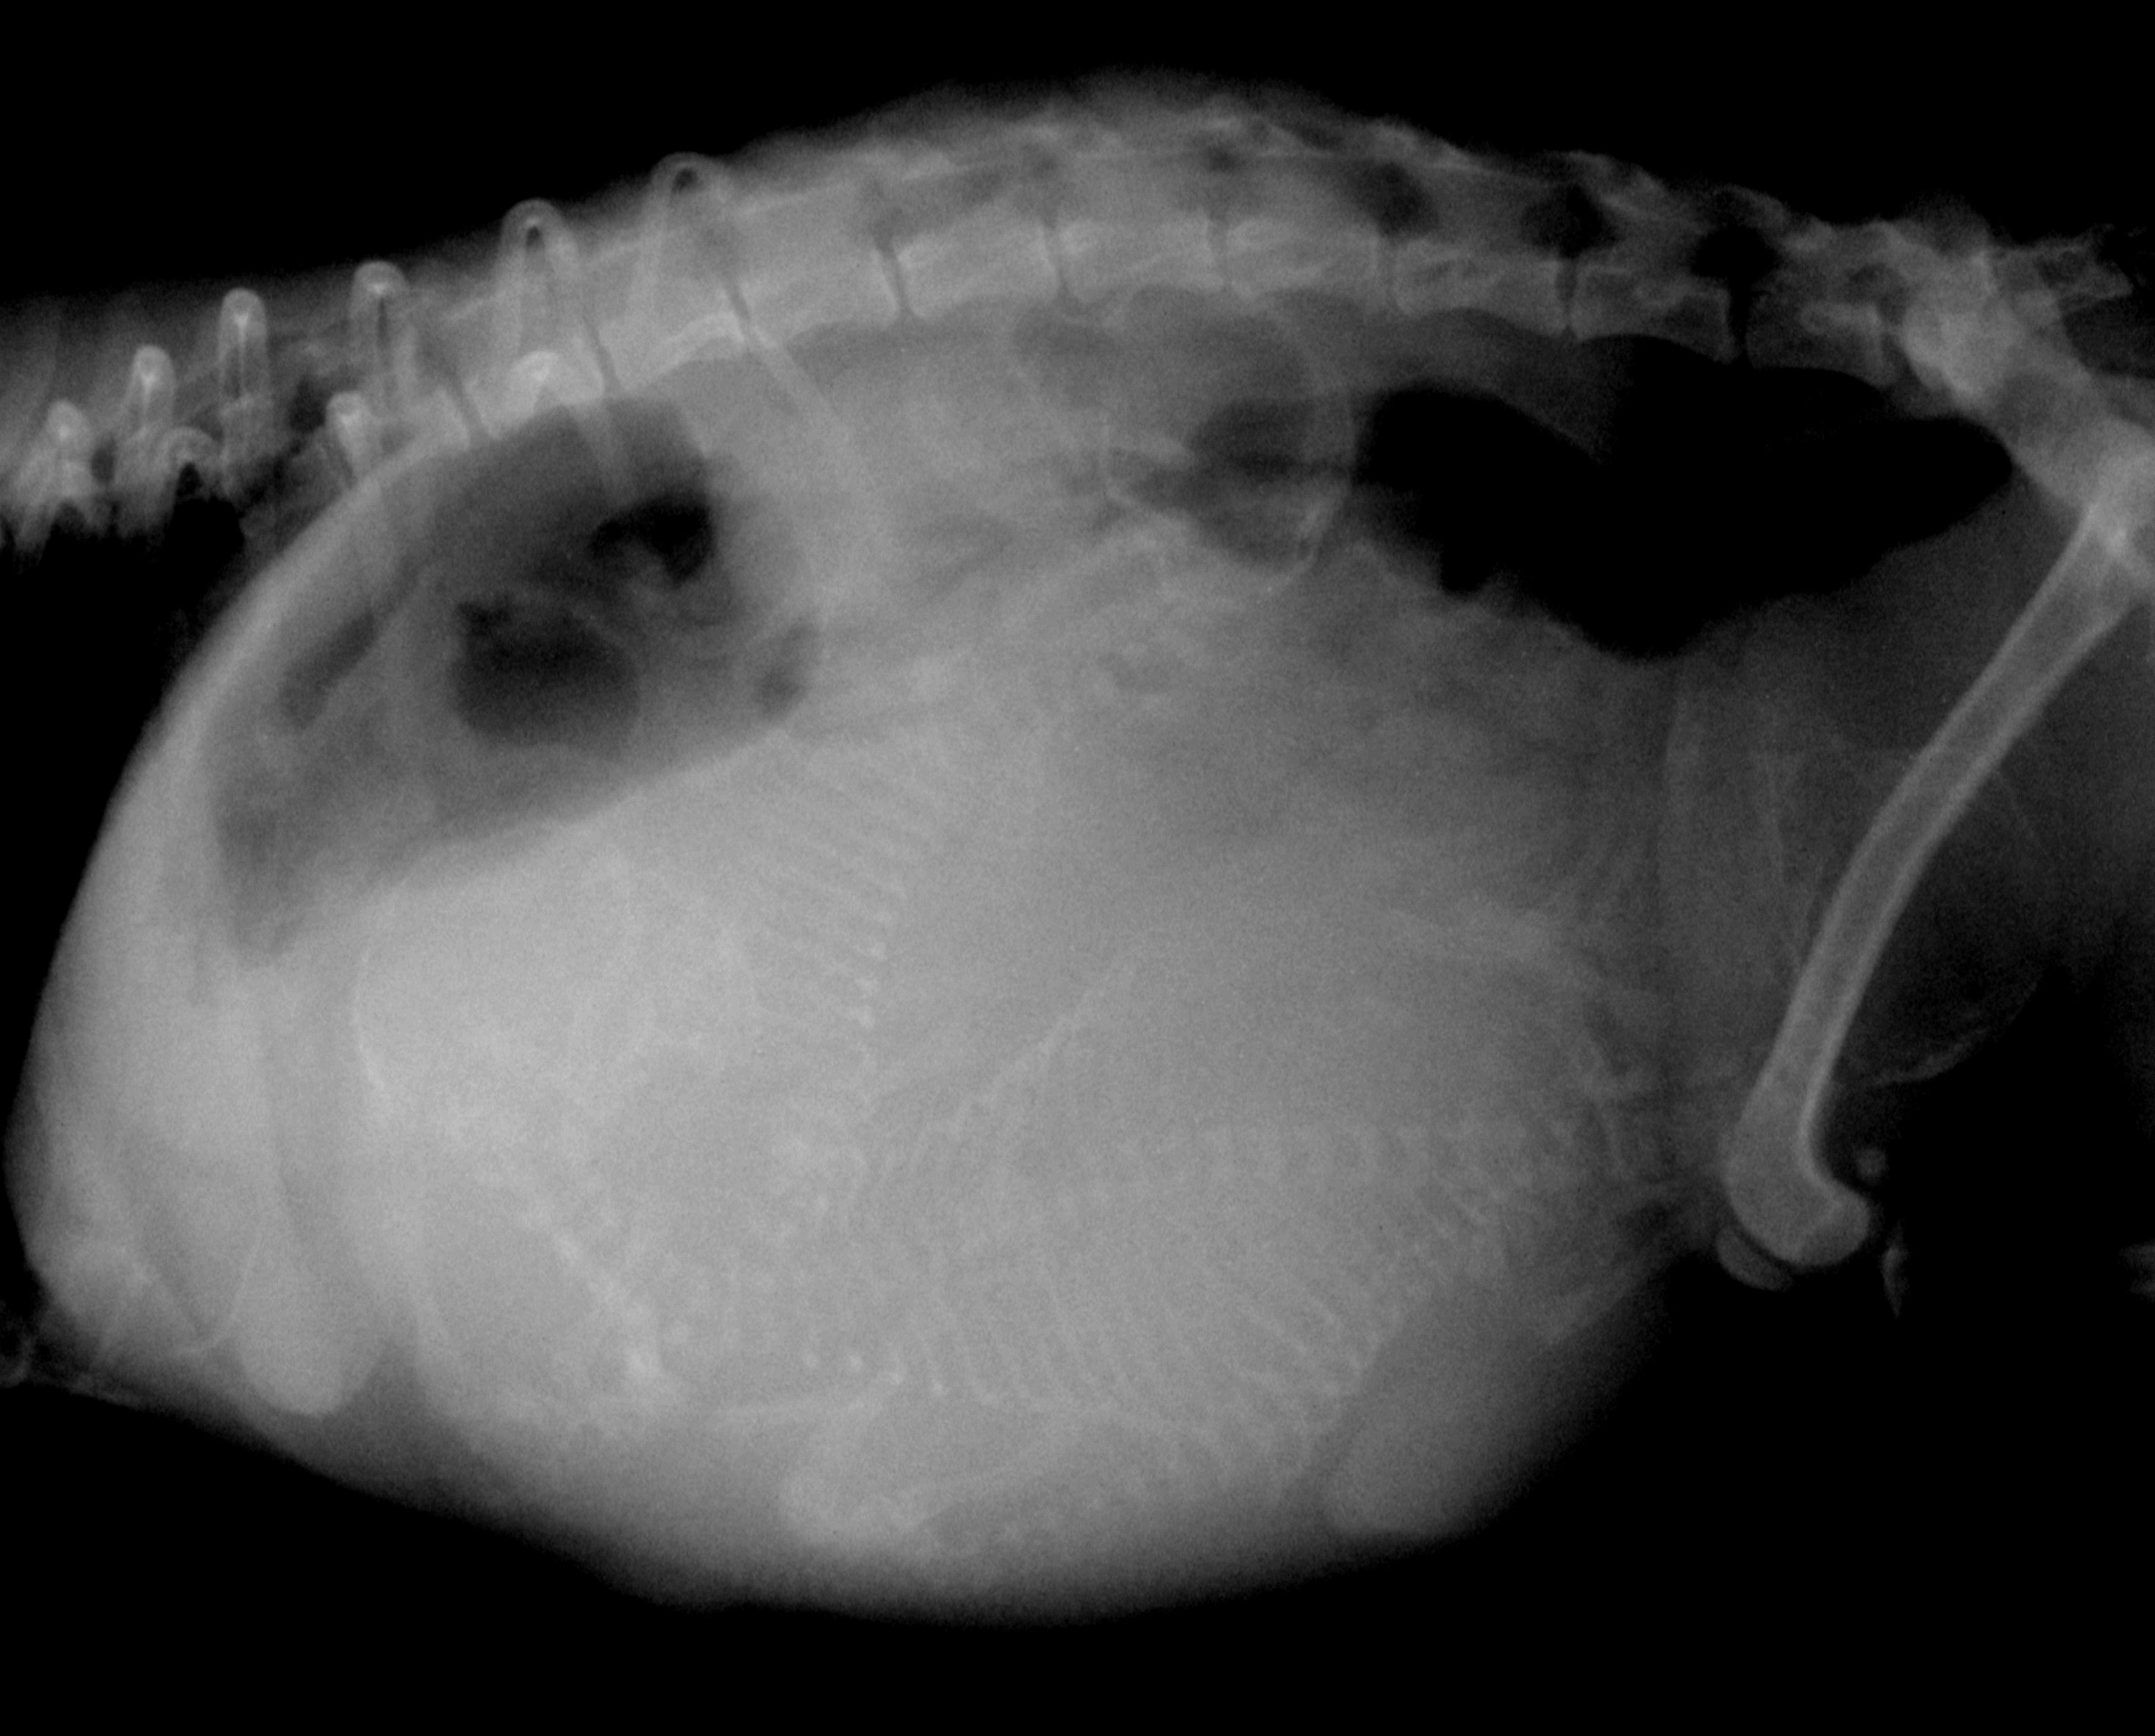

陰部からは羊膜の一部が露出しており、レントゲン検査にて3頭の子犬を確認しました。

↑お腹の中に3頭の子犬がいるのが確認できます